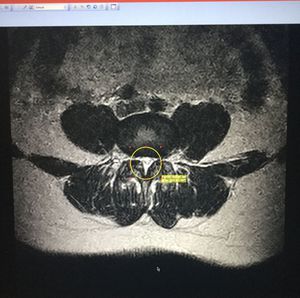

Spinal stenosis occurs when the space around the spinal cord narrows. This puts pressure on the spinal cord and the spinal nerve roots, and may cause pain, numbness, or weakness in the legs. [triangle shape]

Compression of neurons' axon reduce the impulses / action potential transmission